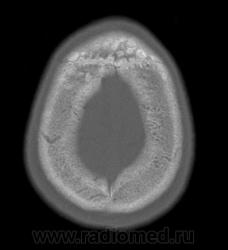

Это болезнь Бурневилля - одна из форм факоматозов?

Да, это болезнь Бурневилля-Прингла, один из видов факоматоза. Врожденное заболевание, развивается из-за нарушений в одной из хромосом.

На УЗИ выявлены множественные ангиомиолипомы почек.